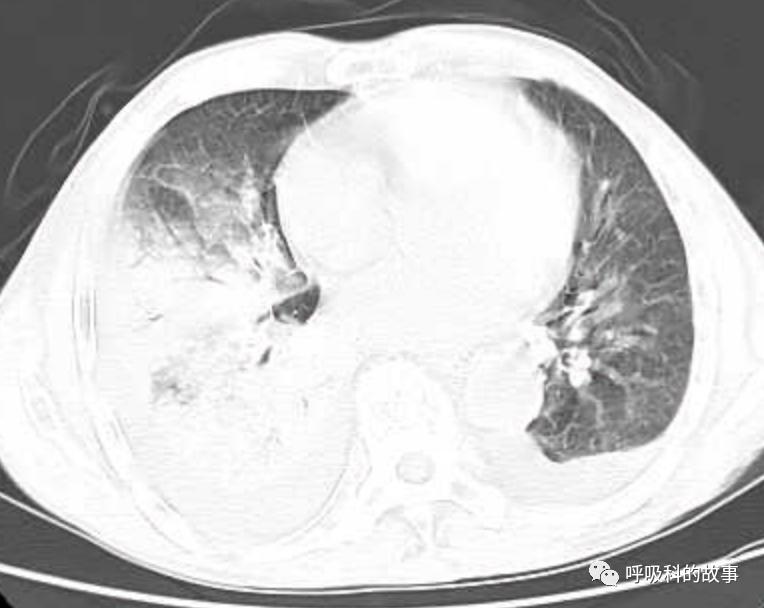

接着,我打开电脑看病历:患者,男,68岁,主诉:发热、头痛伴乏力10余天,咳嗽4天。肺部CT一看是右下叶大片实变肺炎,双侧少量胸腔积液,两上肺内中带片絮状斑片状影。2020.11.30 在外院检查 PCT 7.42ng/ml,ALT 199U/L,AST 250U/L,白蛋白24.7g/L,CRP 108.7mg/L,乳酸脱氢酶LDH388U/L(正常50-240),钾3.27mmol/L;血常规:白细胞4.9*10^9/L,中性85.2%。在外院给予了亚胺培南2天和本院美罗培南治疗2天后,效果并不理想。

(6)肺部影像以大叶性肺炎为主,其他部分是合并肺水肿的影像;